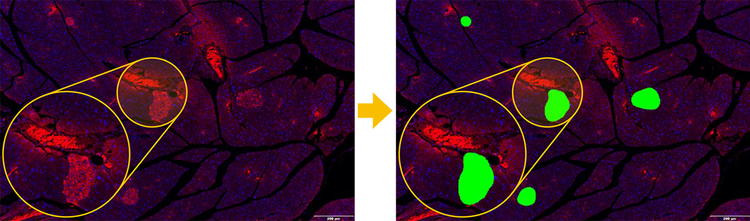

Let Deep Learning Do the Work for You

• Train custom neural networks: Detect difficult objects and apply them to the TruAI solution in one click

• Build and share model libraries: Create application-specific neural network libraries and share them with collaborators to support standardized workflows

• Use pretrained models: Segment nuclei and cells instantly for common applications without training a model*

The figure presents an example of selective detection performed using a neural network trained to identify pancreatic islets (PIs). a) Overview of a rat pancreas section stained with fluorescent labels (Alexa Fluor 594, shown in yellow) at 4X magnification. b) and c) Higher-magnification images of two pancreatic islets. d) Final scans (DAPI in blue and Alexa Fluor 594 in yellow) superimposed on the overview image. Only two regions containing pancreatic islets were rescanned at higher magnification (40X).

TruAI technology, powered by deep learning, enhances image analysis accuracy and improves workflow efficiency. Traditional threshold-based methods struggle to extract shape features from samples and accurately identify target areas. With TruAI, users can train the system by selecting pancreatic islet features in a pancreas sample. The system then automatically and precisely detects only the pancreatic islets, allowing for quick and accurate measurement of their number and size.